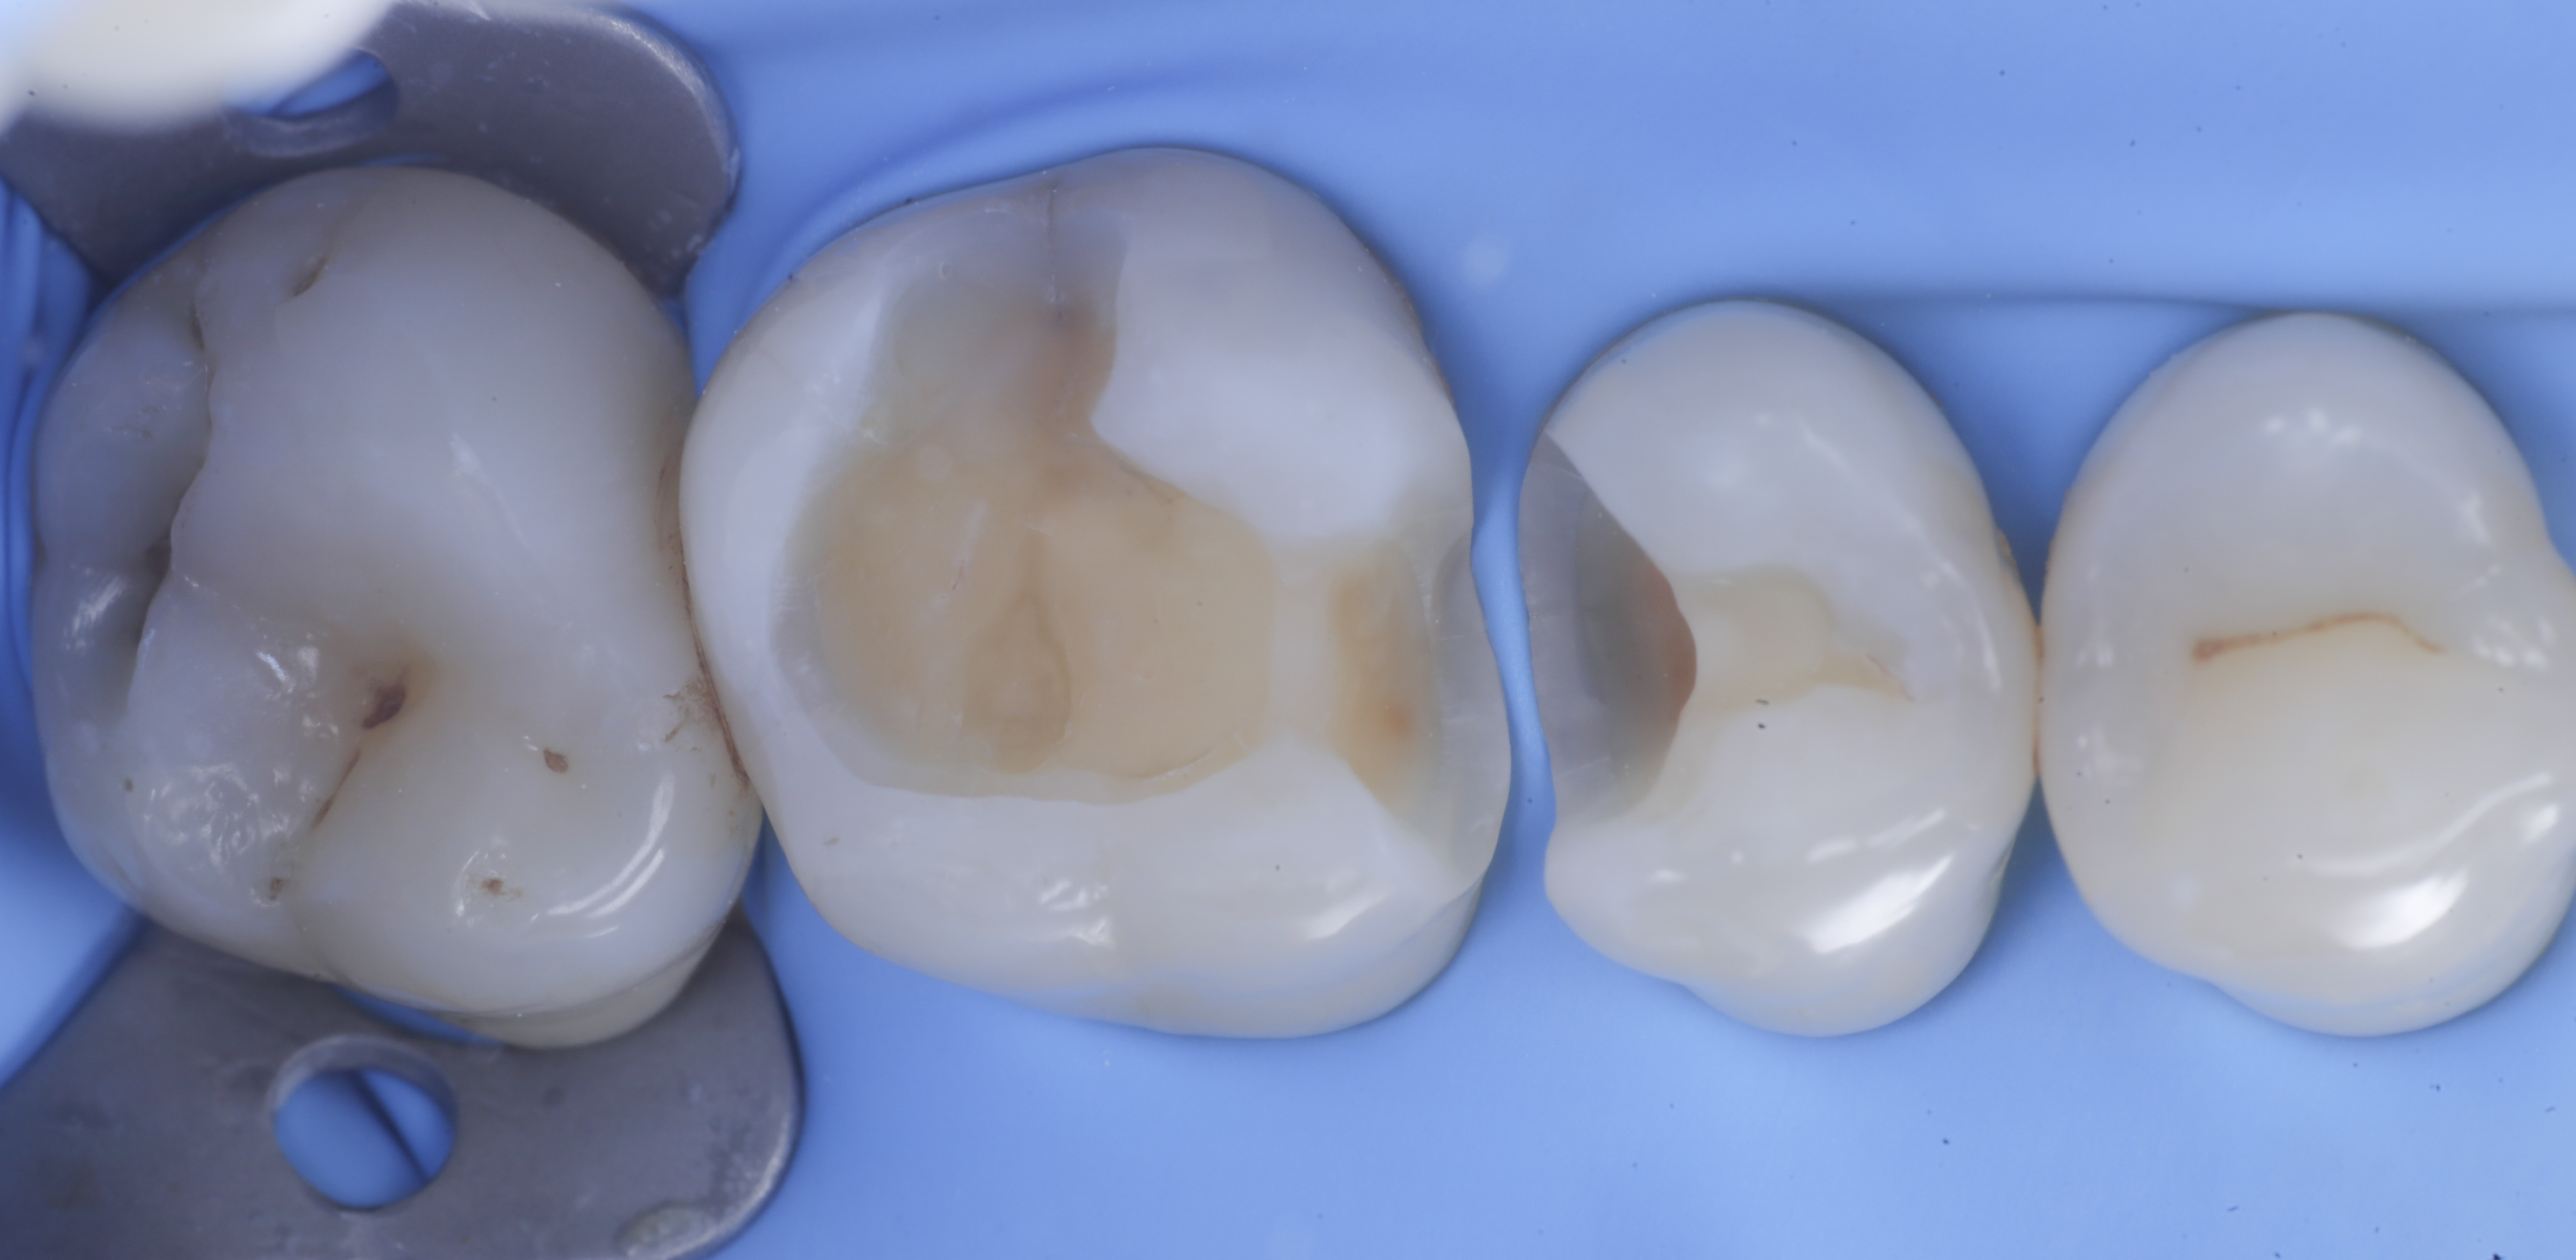

foto 6 Aspetto occlusale delle pareti interprossimali appena create

foto 7 Aspetto vestibolare delle pareti interprossimali appena create

A questo punto si procede con la stratificazione e modellazione di una delle due pareti inter-prossimali e si polimerizza. Si elimina quindi la matrice della parete appena eseguita sposando l’anello che viene immediatamente rialloggiato.

Successivamente, eliminato lo spessore dato dalla seconda matrice, si procede con la creazione della seconda parete.

Trasformate le cavita da II classi a I classi si procede con la classica modellazione cuspide per cuspide, sfruttando le caratteristiche meccaniche e anche estetiche dei materiali compositi bulk.